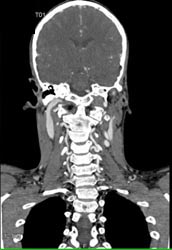

Carotid Artery Ectasia